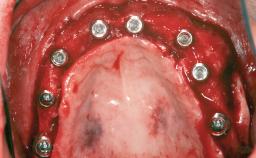

Ridge Preservation and Implant Placement for a Fixed Dental Prosthesis After a Car Accident

# of Teeth 6

# of Implants 4

Type of Implants One-Piece|Reduced-Diameter